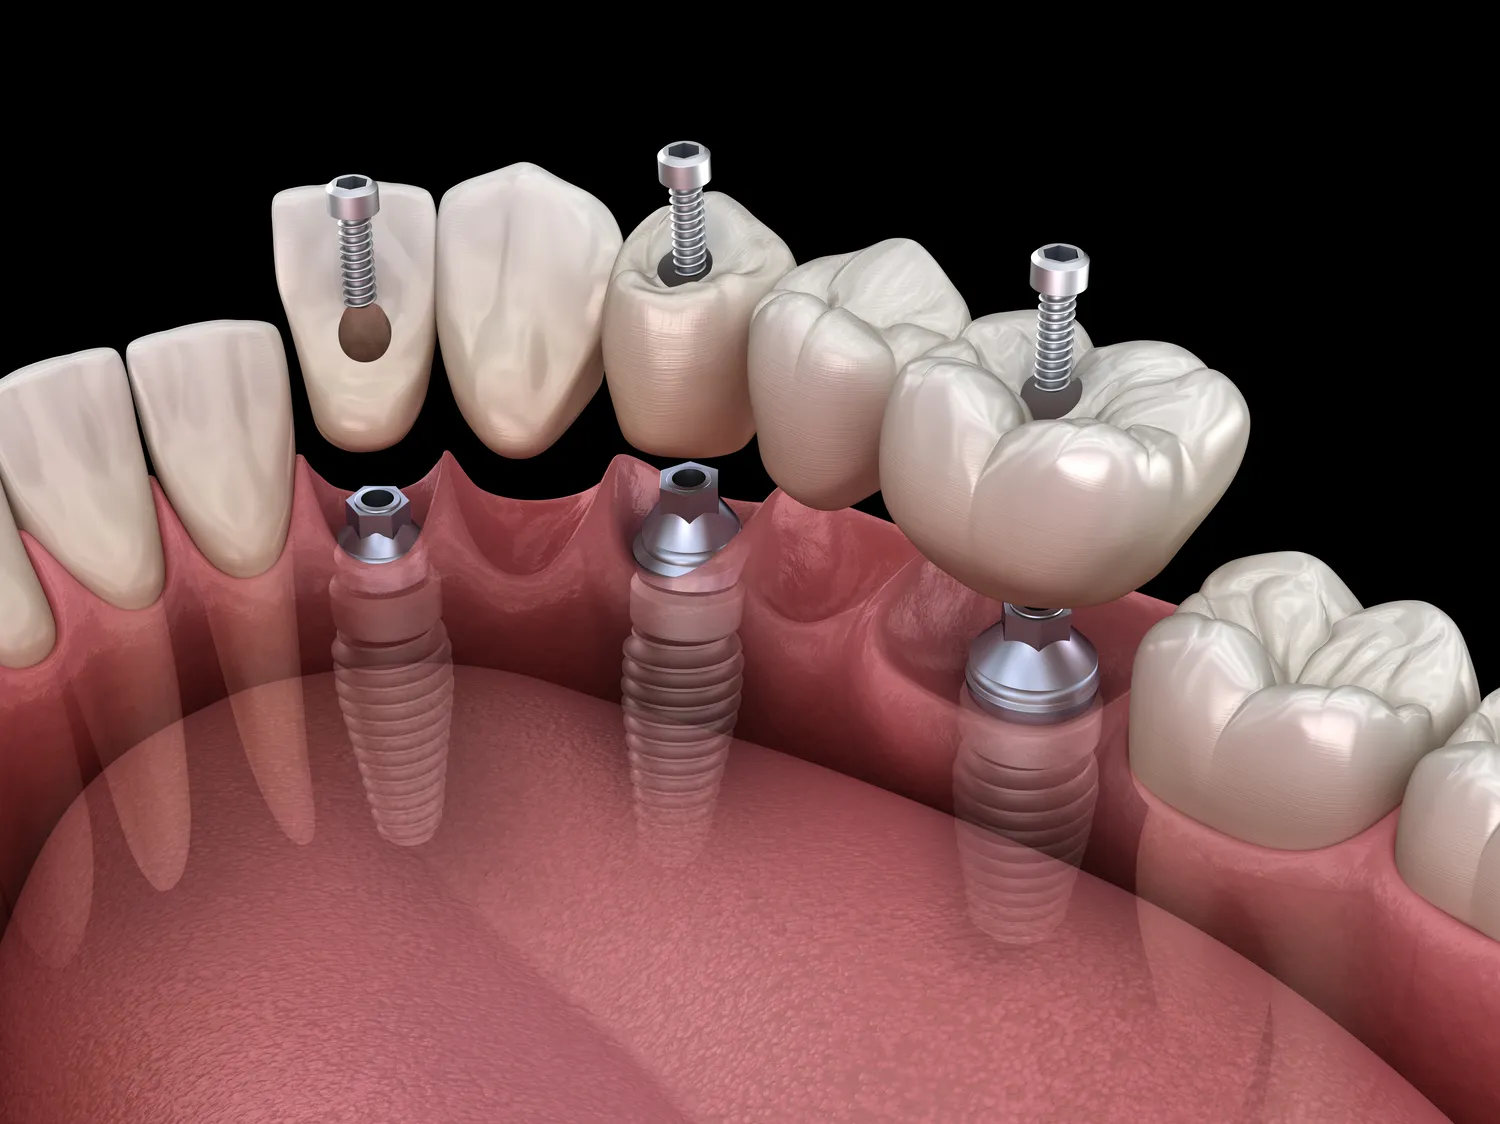

Proces zakupu implantów w jeden dzień w Gryficach rozpoczyna się od konsultacji ze specjalistą, który oceni stan zdrowia pacjenta oraz zaproponuje odpowiednie rozwiązania. Na tym etapie lekarz przeprowadza szczegółowy wywiad medyczny oraz wykonuje niezbędne badania diagnostyczne, takie jak zdjęcia rentgenowskie czy tomografia komputerowa. Dzięki tym informacjom możliwe jest dokładne zaplanowanie zabiegu oraz wybór odpowiednich implantów. Po ustaleniu planu leczenia pacjent przystępuje do zabiegu wszczepienia implantów. W trakcie jednego dnia lekarz wykonuje wszystkie niezbędne czynności, aby pacjent mógł opuścić gabinet z nowymi zębami. Po wszczepieniu implantów następuje natychmiastowe umocowanie korony protetycznej, co pozwala na pełne funkcjonowanie zębów już tego samego dnia. Ważnym elementem tego procesu jest również edukacja pacjenta dotycząca pielęgnacji nowego uzębienia oraz zaleceń pooperacyjnych.

Technologie wspierające proces wszczepiania implantów w jeden dzień w Gryficach stale się rozwijają i przyczyniają się do zwiększenia efektywności oraz bezpieczeństwa zabiegów stomatologicznych. Jednym z kluczowych narzędzi jest tomografia komputerowa, która pozwala na dokładne zobrazowanie struktury kości oraz tkanek miękkich wokół miejsca planowanego wszczepienia implantu. Dzięki temu lekarze mogą precyzyjnie zaplanować zabieg oraz uniknąć potencjalnych komplikacji związanych z anatomicznymi uwarunkowaniami pacjenta. Kolejną innowacją jest zastosowanie technologii CAD/CAM, która umożliwia cyfrowe projektowanie koron protetycznych i ich szybkie wykonanie w laboratoriach dentystycznych. Dzięki temu możliwe jest dostosowanie kształtu i koloru korony do indywidualnych potrzeb pacjenta już tego samego dnia po wszczepieniu implantu. Również techniki chirurgiczne takie jak piezochirurgia czy laseroterapia znacząco zwiększają precyzję zabiegów oraz minimalizują uszkodzenia tkanek miękkich, co przekłada się na szybszy proces gojenia i mniejsze ryzyko powikłań.